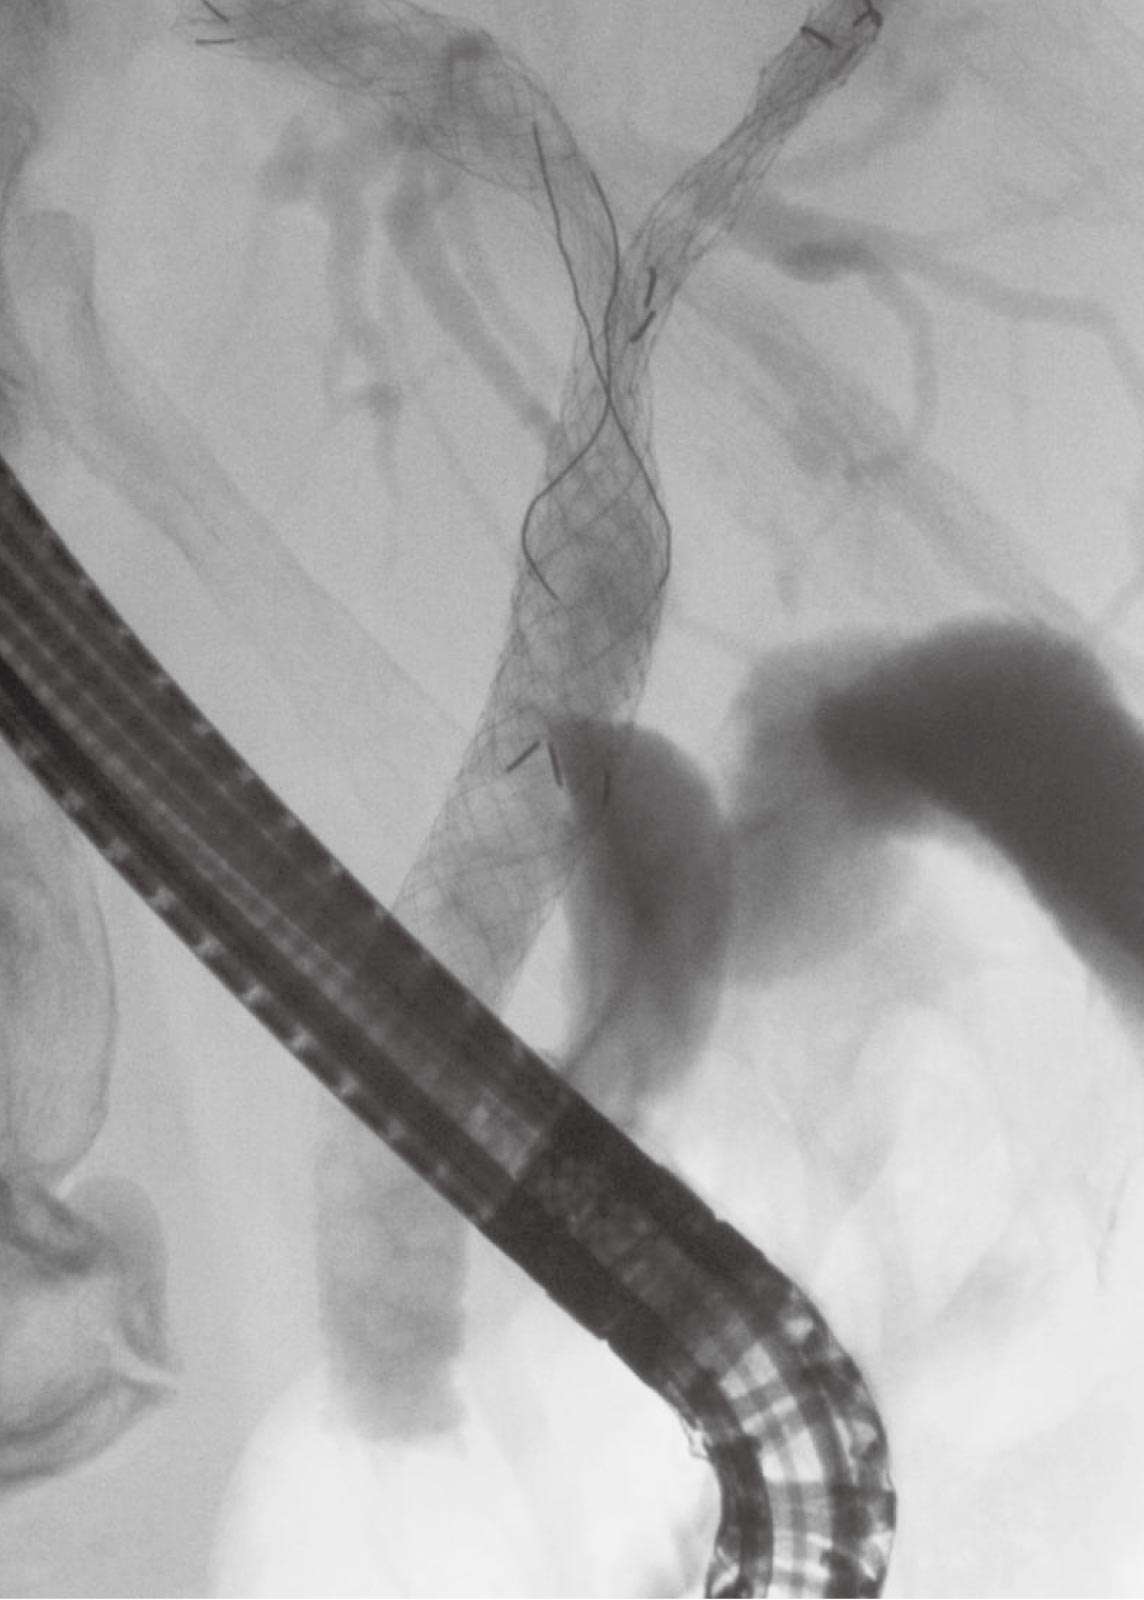

金属ステント留置例

1. 左右の胆管合流部が腫瘍により閉塞しています。

2. 左右の胆管にそれぞれ金属ステントを留置しています。